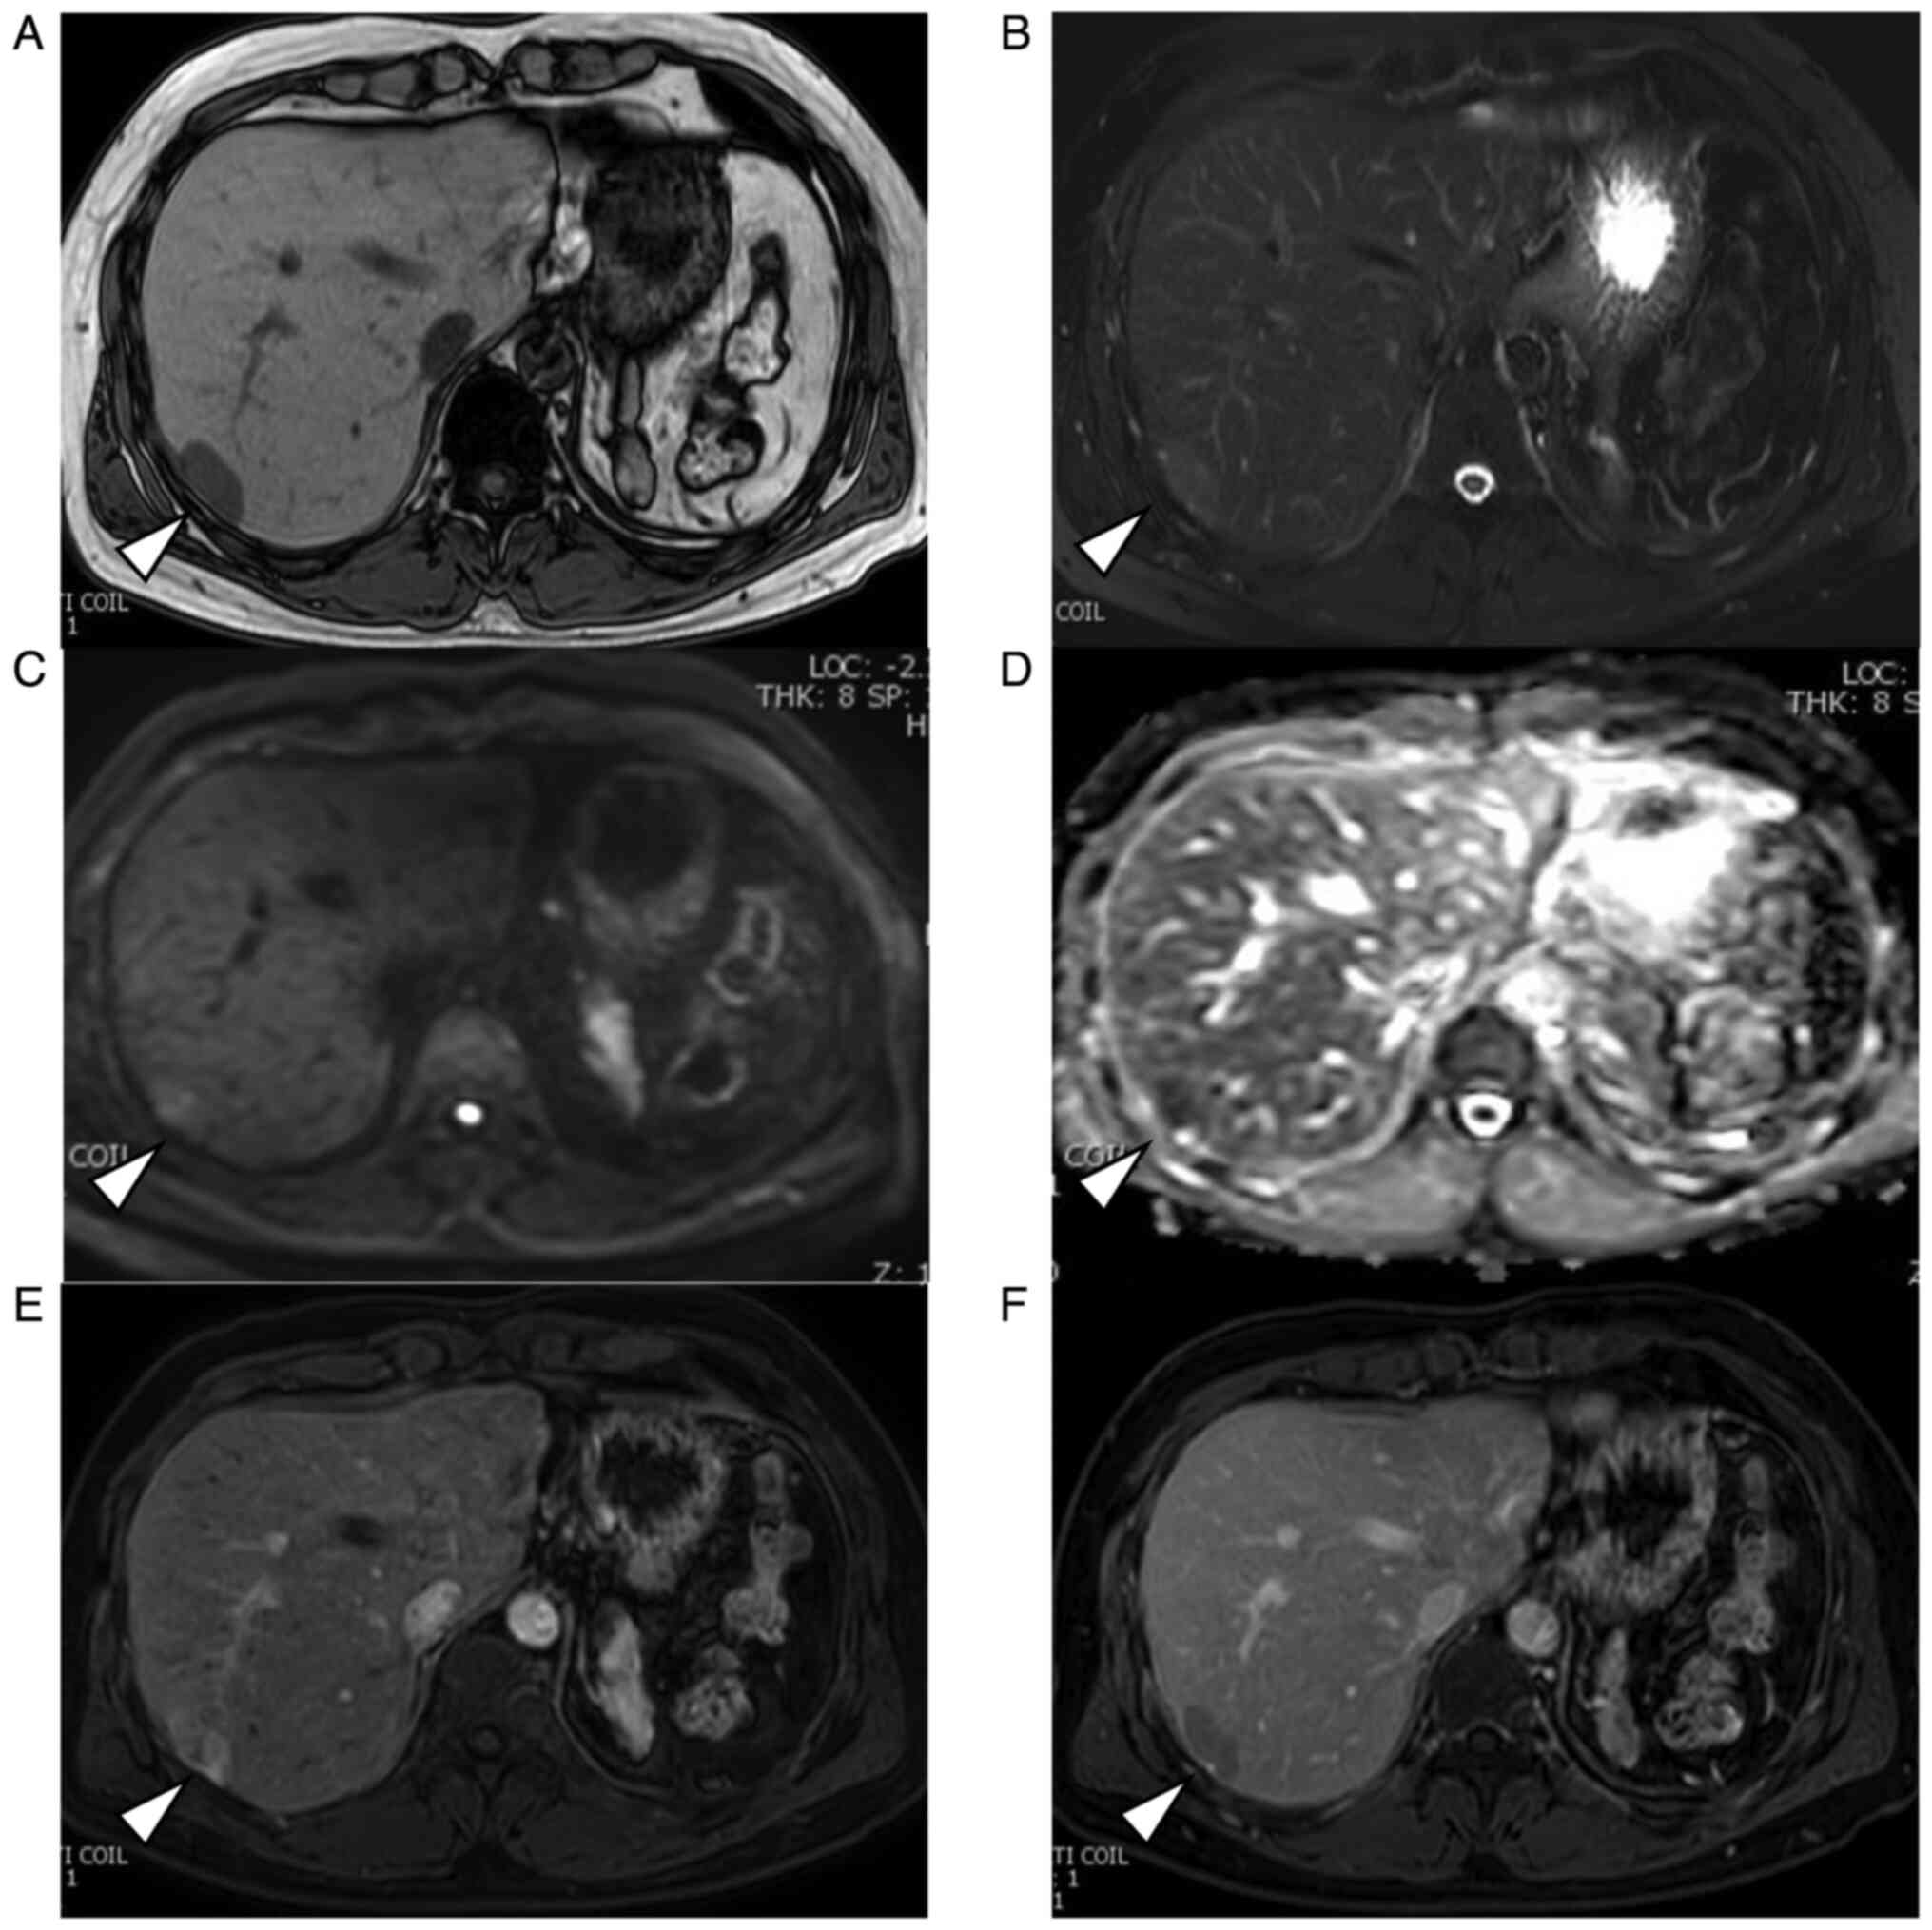

Abdominal ultrasonography (US) revealed a 2.4x1.4 cm isoechoic lesion with a hypoechoic zone at the margins in segment 7 of the right lobe of the liver (Fig. 1A). Abdominal plain-computed tomography (CT) revealed a hypodense mass measuring 2.5x1.7 cm (Fig. 1B). Abdominal magnetic resonance imaging (MRI) revealed a homogeneously hypointense mass in T1-weighted images and hyperintensity in T2-weighted images (Fig. 2A and B). The mass showed a heterogeneous hyperintensity in diffusion-weighted images and signal reduction in apparent diffusion coefficient. (Fig. 2C and D). After injecting gadoxetic acid, the lesion appeared strongly heterogeneous and hyperintense during the early phase and relatively hypointense during delayed phase that is ‘washout pattern’ (Fig. 2E and F). An indication of a pseudocapsule was also seen.

Figure 2

Magnetic resonance imaging of the IHS (arrows). The IHS was detected with (A) a homogeneous hypointensity in T1-weighted images, (B) slight hyperintensity in T2-weighted images. (C) Lesion showed a heterogeneous hyperintensity in diffusion-weighted images and (D) signal reduction in apparent diffusion coefficient. After the injection of gadoxetic acid, (E) the lesion appeared heterogeneously hyperintense during the early phase and (F) relatively hypointense during the delayed phase. HIS, intrahepatic splenosis.

The radiographic appearance of IHS generally varies. Typical findings are hypodense areas on non-contrast CT. Following contrast administration, the lesions are hyperdense in the arterial phase, iso-dense in the portal venous phase, and hypodense in the delayed phase (3,14). On MRI, IHS is usually described as areas of homogeneous hypo-intensity in T1WI and hyperintensity in T2WI (10). Following contrast administration, IHS shows a heterogeneous enhancement in the arterial phase, which becomes homogeneous in the later phases (8,9,15). In the delayed phase, the signal intensity of IHS may be lower than that of the liver parenchyma (10). The imaging features are similar to the signal and enhancement patterns of the spleen, usually described as geographic or zebra patterns of enhancement. In the previous studies, 61.5% of patients had typical radiological features. In our case, the enhancement pattern of the tumor in the enhanced MRI showed early enhancement in the arterial phase and washout in the delayed phase that was similar to the radiographic features of moderately differentiated HCC.

There are currently reported to be two dominant mechanisms of IHS occurring. One hypothesis is that an invagination or an exophytic growth of splenic tissue directly seeded into the liver capsule. With this mechanism, the most frequent site of IHS is the area surrounded by the left lobe and the diaphragm because it can be easily seeded with splenic tissue during splenectomy (14,16-18). The other is that hematogenous spread due to the entry of an erythrocyte progenitor cell into the portal venous system. In the latter pattern, the margin between IHS and liver parenchyma is usually unclear (2,19,20). In our case, tumor happened to metastasize in the right lobe near the inferior phrenic vessels without seeding at the most frequent site, and it was extrahepatically fed by these vessels. The tumor showed early enhancement in the arterial phase and washout in the delayed phase that was characteristic imaging pattern for HCC, although IHS shows a heterogeneous enhancement in the arterial phase, and homogeneous in the later phases (8,9,15). In our case, IHS was extrahepatically fed, so that the radiological findings were typical for HCC. It was difficult to make a correct diagnosis of IHS preoperatively. Surgical procedure was successfully performed.